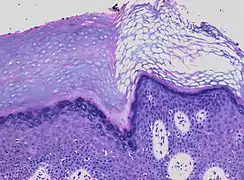

Early actinic keratosis with parakeratosis, with black arrows indicating one of multiple retained nuclei in the stratum corneum

Parakeratosis is a mode of keratinization characterized by the retention of nuclei in the stratum corneum.[1] In mucous membranes, parakeratosis is normal.[2] In the skin, this process leads to the abnormal replacement of annular squames with nucleated cells. Parakeratosis is associated with the thinning or loss of the granular layer and is usually seen in diseases of increased cell turnover, whether inflammatory or neoplastic. Parakeratosis is seen in the plaques of psoriasis and in dandruff.